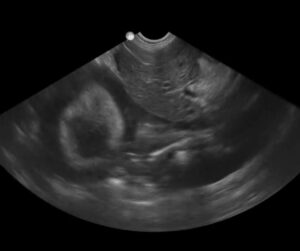

The sonographic finding of the gallbladder halo sign has been reported to be helpful as a marker for anaphylaxis (AX) in dogs since their shock organ (where most mast cells reside) is their liver and gastro-intestinal tract (unlike humans and cats that have the lungs as their shock organ). The massive histamine release causes acute hepatic congestion due to constriction of hepatic venous outflow (Quantz, JVECC 2009). Of course, other signs are helpful for the diagnosis of AX including acute gastrointestinal signs (vomiting and defecating) with collapse, an elevated lactate, an elevated alanine transaminase (ALT). and hemoconcentration. The image below shows a massive gallbladder halo sign at the AFAST DH view at triage (within minutes of patient arrival). In the following image, you can clearly see pericardial effusion surrounding the heart as imaged at the DH view. Take our AFAST Course to learn more; link for more information- Learn more about AFAST!